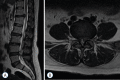

Surgical treatment of the degenerative disc disease has evolved from traditional open spine surgery to minimally invasive spine surgery including endoscopic spine surgery. Constant improvement in the imaging modality especially with introduction of the magnetic resonance imaging, it is possible to identify culprit degenerated disc segment and again with the discography it is possible to diagnose the pain generator and pathological degenerated disc very precisely and its treatment with minimally invasive approach. With improvements in the optics, high resolution camera, light source, high speed burr, irrigation pump etc, minimally invasive spine surgeries can be performed with various endoscopic techniques for lumbar, cervical and thoracic regions. Advantages of endoscopic spine surgeries are less tissue dissection and muscle trauma, reduced blood loss, less damage to the epidural blood supply and consequent epidural fibrosis and scarring, reduced hospital stay, early functional recovery and improvement in the quality of life & better cosmesis. With precise indication, proper diagnosis and good training, the endoscopic spine surgery can give equally good result as open spine surgery. Initially, endoscopic technique was restricted to the lumbar region but now it also can be used for cervical and thoracic disc herniations. Previously endoscopy was used for disc herniations which were contained without migration but now days it is used for highly up and down migrated disc herniations as well. Use of endoscopic technique in lumbar region was restricted to disc herniations but gradually it is also used for spinal canal stenosis and endoscopic assisted fusion surgeries. Endoscopic spine surgery can play important role in the treatment of adolescent disc herniations especially for the persons who engage in the competitive sports and the athletes where less tissue trauma, cosmesis and early functional recovery is desirable. From simple chemonucleolysis to current day endoscopic procedures the history of minimally invasive spine surgery is interesting. Appropriate indications, clear imaging prior to surgery and preplanning are keys to successful outcome. In this article basic procedures of percutaneous endoscopic lumbar discectomy through transforaminal and interlaminar routes, percutaneous endoscopic cervical discectomy, percutaneous endoscopic posterior cervical foraminotomy and percutaneous endoscopic thoracic discectomy are discussed.